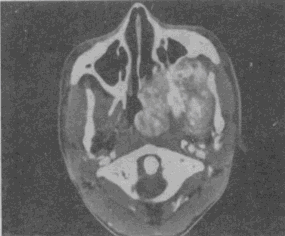

男,19岁,左侧鼻腔反复出血1年余,CT、MRI扫描如图,最可能的诊断是 YZ332_5_54_63.gif YZ332_5_54_63_1.gif YZ332_5_54_63_2.gif

• C.鼻咽部青年纤维血管瘤